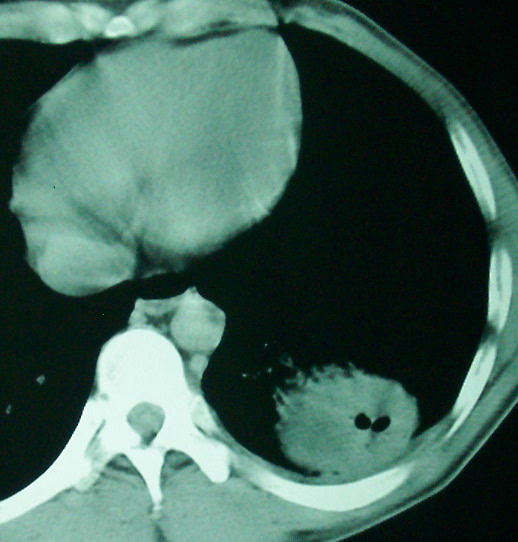

空洞内可见小结节样密度影考虑合并真菌感染

左下叶肺癌,双肺转移

左下肺病灶除了明显的厚壁空洞 气液平外,明显见壁结节,另两肺多发小结节,综合考虑:左下肺周围性肺癌伴肺内转移.